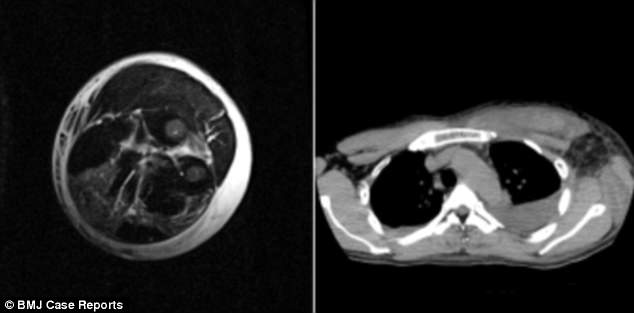

В апреле 2016 года, по данным BMJ Case Reports, в апреле 2016 года неизвестный мужчина 38 лет обратился в больницу с жалобами на сильную боль в левой руке.

За восемь часов до госпитализации пациент упал в своем саду, и у него на левом предплечье появился отек с терпимой болью.

Сканирование не выявило переломов костей или внутреннего кровотечения, но его боль и опухоль усилились, что заставило врачей предположить, что он страдал от ОКС.

Помимо развития косоглазия и двоения в глазах, тесты выявили признаки повреждения и воспаления печени.

Вскоре после его прибытия в больницу была проведена операция, чтобы снять опухоль и вымыть предполагаемый яд из пораженного участка.

Хотя пациенту была назначена высокая доза антибиотиков, всего через два дня у него появился избыток жидкости в левом легком и вокруг сердца. Он также потерял способность двигать пораженной рукой и рукой.

После проведения гемодиализа, который очищает кровь, на четвертый день состояние пациента постепенно улучшилось, и, наконец, через 32 дня он был выписан с полным движением кисти и руки.

Слева: показывает избыток жидкости в тканях и мышцах левой руки первого пациента. Справа: показать «вода в легких» и избыток жидкости в области непосредственно перед сердцем или над его сердцем

Слева и справа: показать избыток жидкости в артерии, снабжающей кровью правую ногу второго пациента